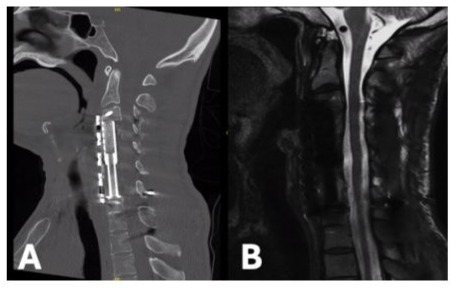

43-year-old female with past medical history significant for IVDU, chronic HCV, endocarditis, and depression returned to the hospital with a chief complaint of BLE paralysis and BUE paresis for two days. Past surgical history includes C6-C7 ACCF three months prior for MRSA osteomyelitis. Exam findings significant for 0/5 motor strength throughout BLEs and 2/5 throughout BUEs. CT Cervical Spine found fracture of the C5 vertebral body with hardware subsidence (Figure 5A). MRI Cervical Spine demonstrated significant canal stenosis with cord compression and large prevertebral abscess (Figure 5B). The patient was placed in cervical traction using Gardner-Wells tongs while in the emergency department. There was moderate improvement in cervical kyphosis, however no improvement in neurologic function. She was then taken to the operating room for revision ACCF extending from C4-T1 using an expandable titanium cage and C2-T2 posterior fixation. Post-operative CT Cervical Spine discovered significant displacement of the anterior hardware and dislodgement of cranial screws (Figure 6A). She returned to the operating room emergently for correction of hardware, with focus on maximizing purchase through increased screw length and diameter (Figure 6B). Postoperatively, the patient’s neurologic exam improved to antigravity throughout. Two days later, she experienced recurrence of BLE paralysis. MRI Cervical Spine discovered diffuse spinal cord swelling throughout the cervical region. She was taken emergently to the operating room for posterior cervical decompression which was completed without complications (Figure 6C). She returned to the intensive care unit intubated. Unfortunately, she soon thereafter developed septic shock from an intra-abdominal source and passed away two weeks later.

Figure 5: Sagittal CT Cervical Spine without Contrast demonstrating osseus destruction and focal cervical kyphosis above the corpectomy hardware (A). Sagittal T2 MRI Cervical Spine without Contrast showing significant cord compression (B).

Figure 6: Post-operative sagittal CT Cervical Spine without Contrast showing significant displacement of the anterior corpectomy cage and plate (A). Repeat CT completed after emergent revision of anterior hardware (B). CT Cervical Spine following posterior cervical decompression (C).